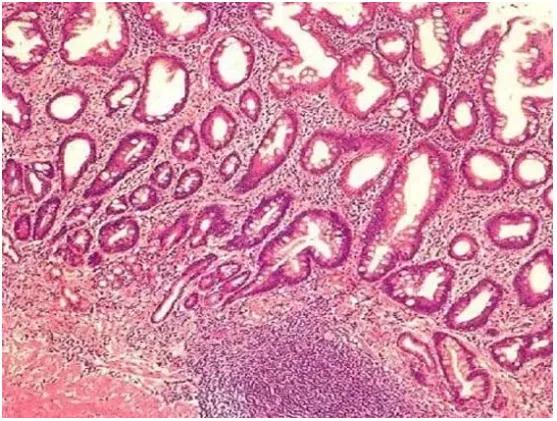

肠化生

胃黏膜上皮细胞类型变成了类似肠道黏膜细胞的形态。肠化生通常出现在胃窦部,且与胃癌发生密切相关。